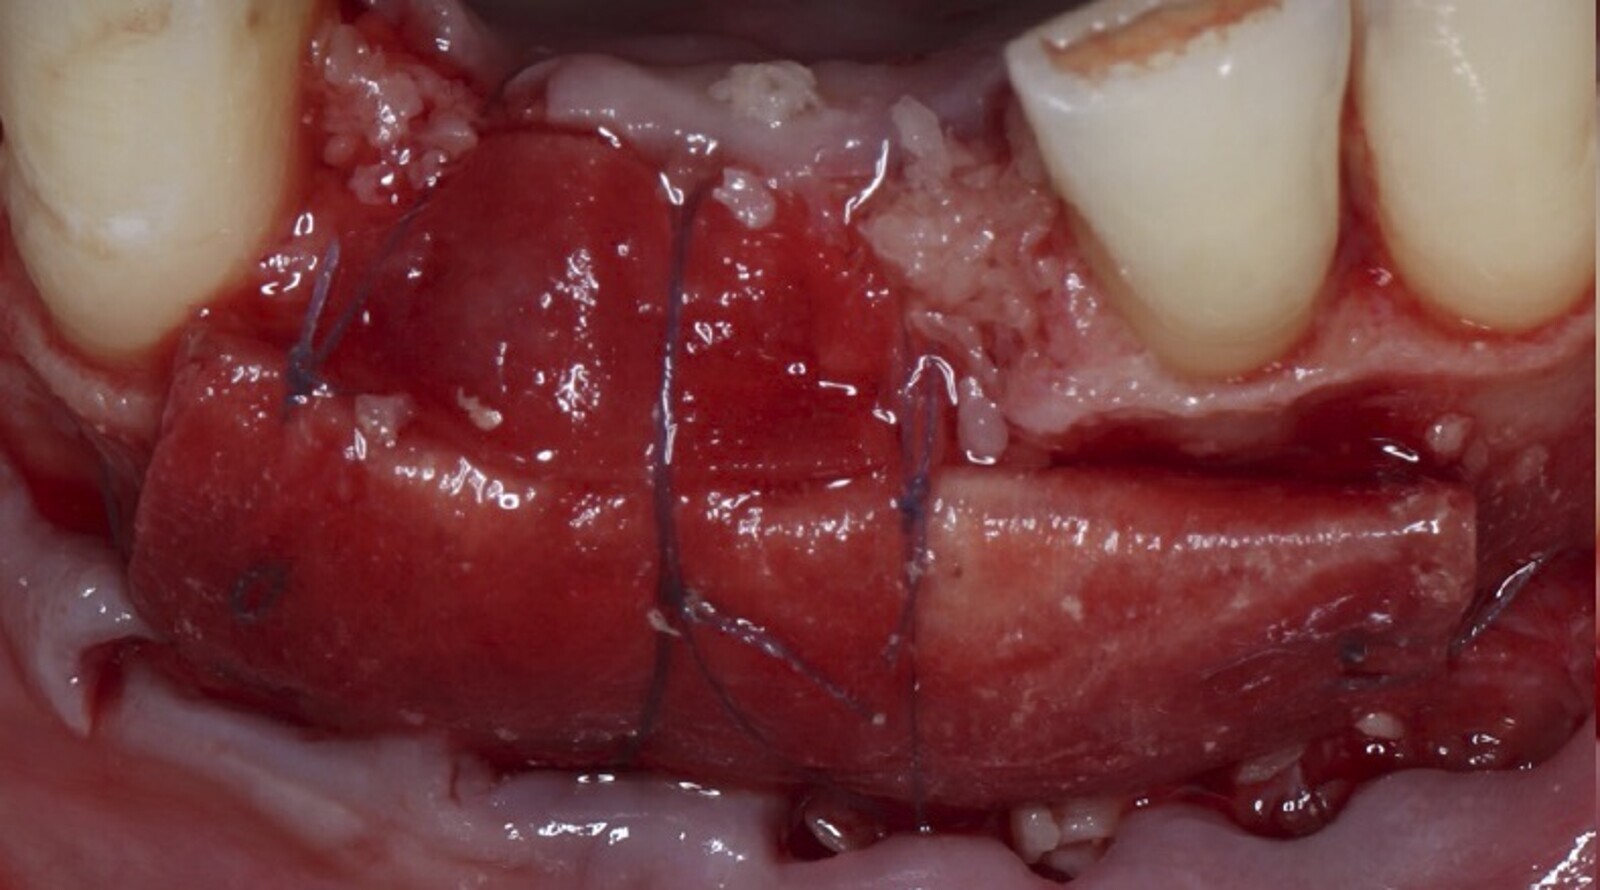

Figura 2. La vitamina D fue útil como terapia coadyuvante para la regeneración ósea. (Foto: Iván Herrera Ustariz/Samia Isaac Tatis)

El tratamiento con vitamina D, muestra un aumento significativo de la densidad ósea periimplantaria, en el contacto del hueso-implante, en una relación 1,5 veces mayor y una mejora, en la micro arquitectura trabecular periimplantaria.[5]

Los resultados de varios estudios concluyen que la suplementación con vitamina D mejora la formación de hueso nuevo alrededor de los implantes dentales.[8]

La vitamina D mejoró la formación de hueso nuevo y el contacto hueso–implante;[7] asimismo, se indicó que la deficiencia de vitamina D tiene un impacto negativo en la formación de hueso cortical periimplantario en ratas ovariectomizadas, lo que se puede manejar con la ingesta de suplementos de la misma. Este estudio sustenta el posible efecto-beneficio de la suplementación nutricional con vitamina D en implantología oral.